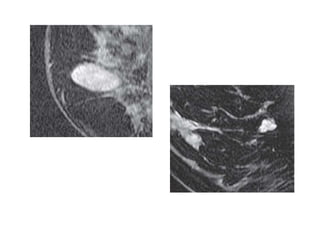

Very high signalon T2-weighted fast spin-echo images that is brighter than fat (on nonfat-suppressed sequences) and substantially brighter than glandular tissue suggests a benign lesion such as a cyst (A, arrow), intramammary lymph node (B, arrows), or fibroadenoma (C).

Most malignancies, unless franklynecrotic, have a signal intensity that is similar to that of fibroglandular tissue